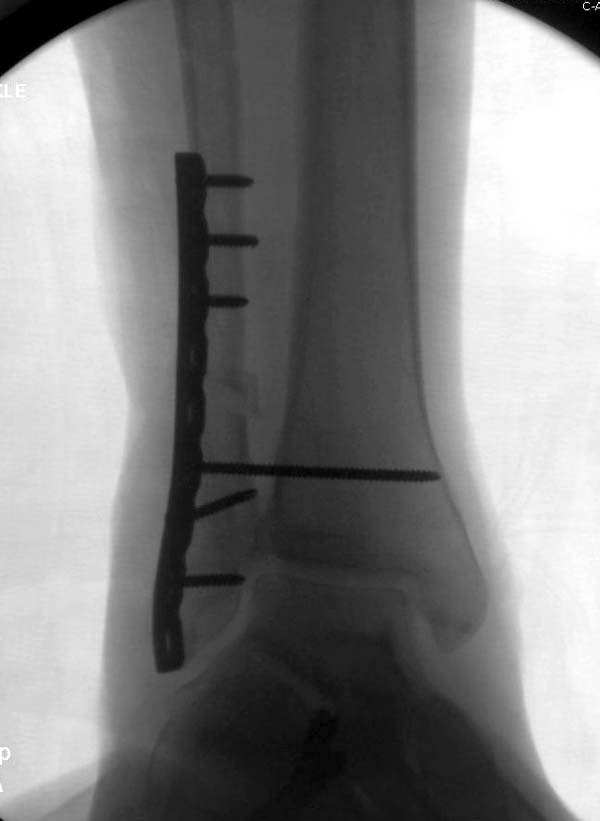

Здесь представлено решение похожей проблемы. Больной в течение года лечился консервативными мерами, и боли в голеностопе были основным показанием к операции.

Проведена обычная стандартная процедура по исправлению неудовлетворительного состояния голеностопного сустава, где кроме удлинения малоберцовой с применением compression tension device за проксимальный конец пластины, проведено замещение трикортикальным графтом из крыла, освобождение синдесмоза и медиальной щели от

фибротических масс с фиксацией.